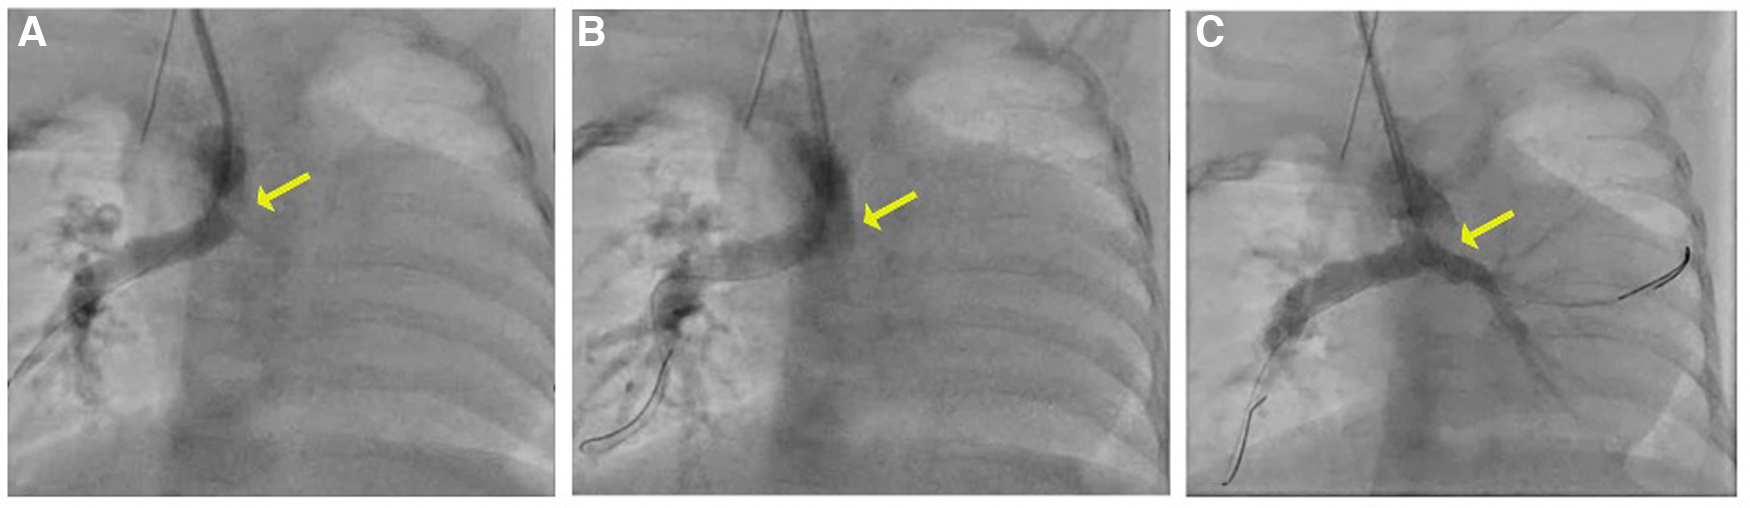

Percutaneous right carotid access was obtained, and a 4-Fr sheath was inserted. A 4-Fr Glide catheter (Terumo) with a 0.035 in. Glidewire (Terumo) was used to access the central shunt. The wire was removed, and an 0.014 in. PT Graphix wire (Boston Scientific) was inserted into the 4-Fr Glide catheter (Terumo) and positioned across the RPA. An angiogram was performed, which demonstrated a thrombus extending from the left pulmonary artery into the distal central shunt. Multiple wires and catheters were used to attempt to access the left pulmonary artery but were unsuccessful in passing through the thrombus. A second wire was placed into the distal right pulmonary artery. A 4-Fr, 50-cm-long Penumbra CAT3 catheter was advanced through the right carotid artery over both wires attached to the Indigo aspiration system, and a thrombectomy was performed. Although no thrombus was detected in the filter, there was a decrease in the size of the thrombus in the central shunt and LPA on serial angiography, with new evidence of flow seen to the distal LPA (Figure 2).

Figure 2

(A) Angiogram with a 4 Fr Glide catheter via the right carotid artery sheath demonstrates thrombus in the mid-to-distal central shunt (yellow arrow) and no contrast seen in the LPA. (B, C) On serial angiography following mechanical thrombectomy, the area of lucency is no longer present and there is improved flow in the LPA.